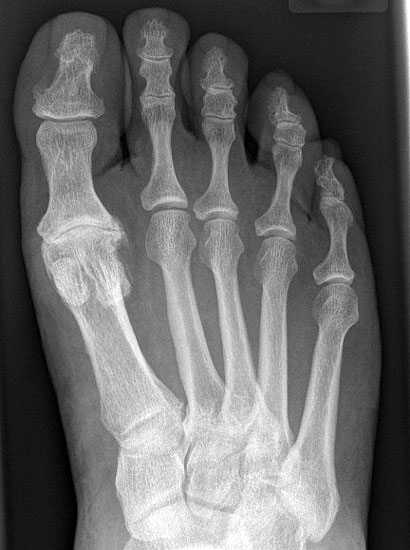

• Röntgenaufnahmen des Vorfußes (unter Belastung) im dorsoplantaren und seitlichen Strahlengang (Abb. 1a+b)

• Beurteilung des Erkankungsstadiums anhand der typischen Arthrosekriterien (Einteilung nach Regnauld) 2

• Beurteilung des Intermetatarsal-Winkels (IMA), des Hallux valgus-Winkels (HVA), mögliche Korrektur der des IMA von 6° durch alleinige Arthrodese, darüber hinaus evtl. zusätzliche MT-I-Korrektur notwendig 101112

• Beurteilung des Metatarsale-Index und der Zehenlänge DI und II, insbesondere nach Voroperationen hinsichtlich einer evtl. notwendigen Verlängerung des ersten Strahls durch Knochenspaninterposition

Die größten Probleme der Arthrodese des MTP-I-Gelenks resultieren aus Fehlpositionierung, Verkürzung des 1. Strahls, Pseudarthrose und Anschlussarthrose des Interphalangealgelenks.

Verkürzung: Vor allem bei präoperativ bereits bestehender relativer Verkürzung des 1. Strahls z.B. bei griechischer Fußform mit relativer Überlänge des. 2. Strahls oder sekundärer Verkürzung durch Voroperationen (z.B. Resektionsarthroplastik nach Keller-Brandes, fehlgeschlagene Arhrodese oder Gelenkarthroplastik, Z. n. Hallux-Valgus-Korrekturosteotomie) ist eine genaue Überprüfung der Längenverhältnisse notwendig, da es durch die Präparation der Arthrodeseflächen immer zu einem zusätzlichen Längenverlust von ca. 5 mm kommt. Bei deutlicher Verkürzung ist entweder eine Knocheninterposition mit trikortikalem Beckenkammspan zur Verlängerung des 1. Strahls oder ggf. die Verkürzung der benachbarten Zehen zu planen.